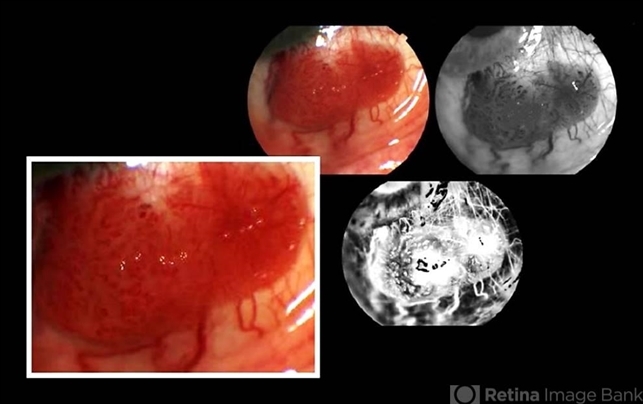

- conjunctival cysts, tumor, papilloma, papilloma conjunctiva

Topcon TRC-50 Dx - Angulation of field photo of 35 Degrees, flash 36, Digital system Imaginet - Description

- Female patient, 26-years-old without complaint of ocular symptoms, only the of spot avermelha in the right eye. Absence of changes in positions of the look. Intraocular pressure visual acuity and fundoscopy without changes.